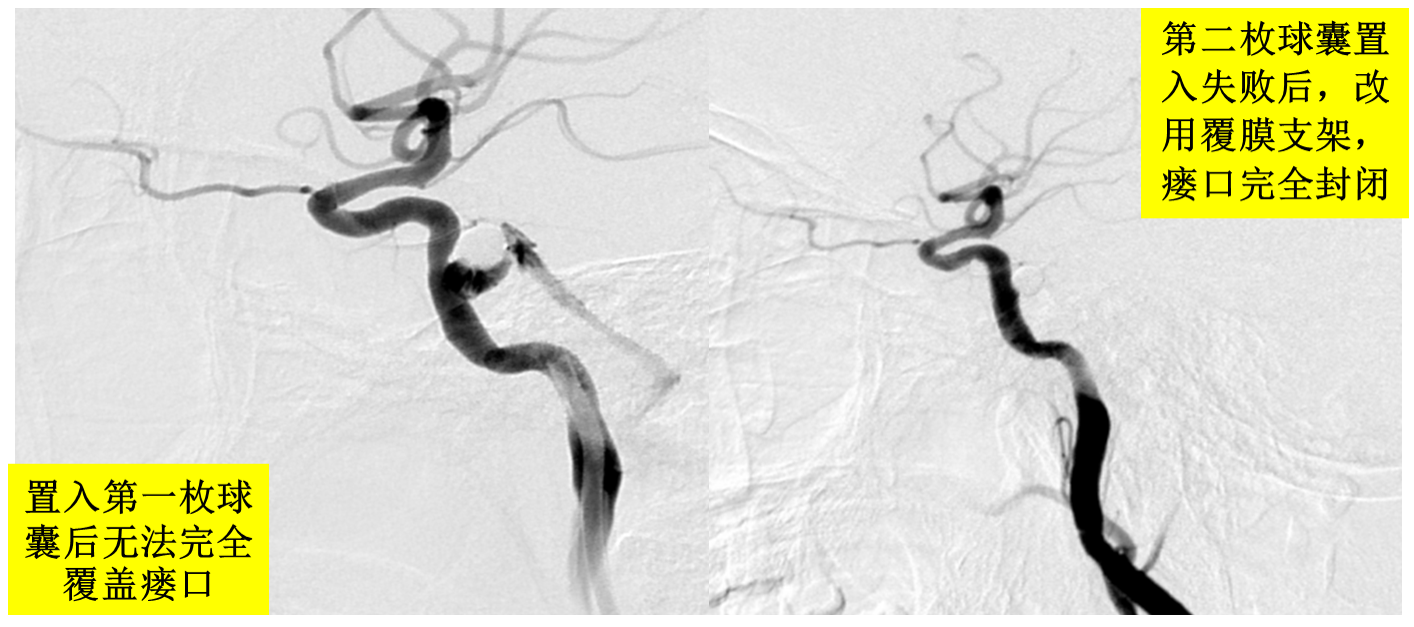

复杂型外伤性颈动脉海绵窦瘘一例治疗

图片尺寸1080x810

一例外伤性颈动脉海绵窦瘘

图片尺寸2000x2667